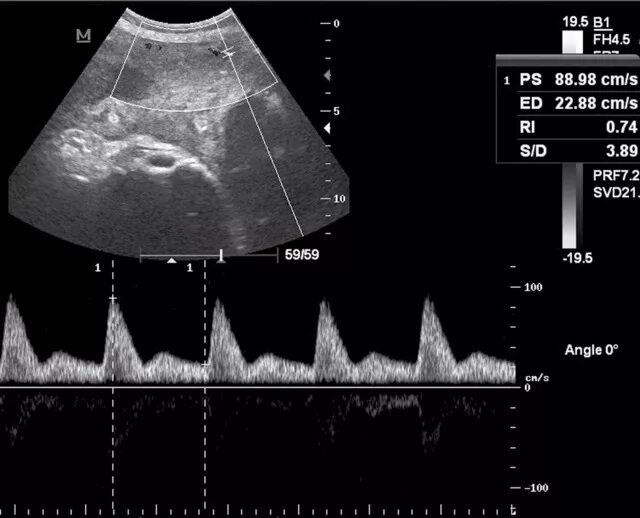

Мппк 1 а степени